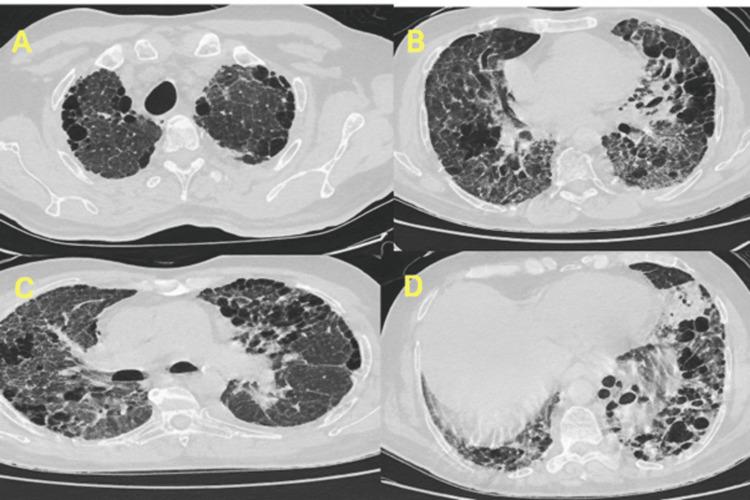

Pulmonary nocardiosis is a rare and often overlooked infection, particularly in individuals without classical immunosuppression. This report describes an unusual presentation of pulmonary infection in a patient with fibrotic interstitial lung disease and a significant history of occupational exposure to aluminum fumes. A 56-year-old male patient presented with progressive respiratory symptoms and hemoptysis, ultimately diagnosed through microbiological culture. Clinical improvement followed targeted antibiotic therapy. This case highlights the importance of considering atypical infections in patients with chronic lung conditions and environmental exposures.

肺诺卡菌病是一种罕见且常被忽视的感染,尤其是在没有典型免疫抑制的个体中。本报告描述了一名患有纤维化间质性肺病且有大量职业性铝烟暴露史的患者肺部感染的不寻常表现。一名56岁男性患者出现进行性呼吸道症状和咯血,最终通过微生物培养确诊。针对性抗生素治疗后临床症状改善。该病例强调了在患有慢性肺部疾病和有环境暴露史的患者中考虑非典型感染的重要性。